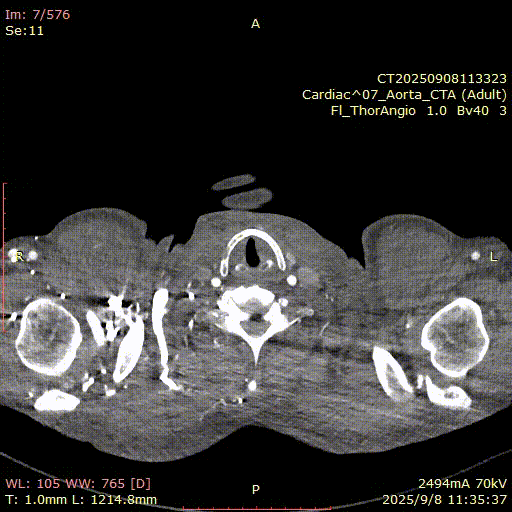

术后CTA

术后一周患者返院进行常规随访检查。CTA检查结果显示:植入支架与血管壁贴合良好,未见内漏征象。患者术前巨大动脉瘤瘤囊已完全血栓化,瘤腔内血流信号消失。